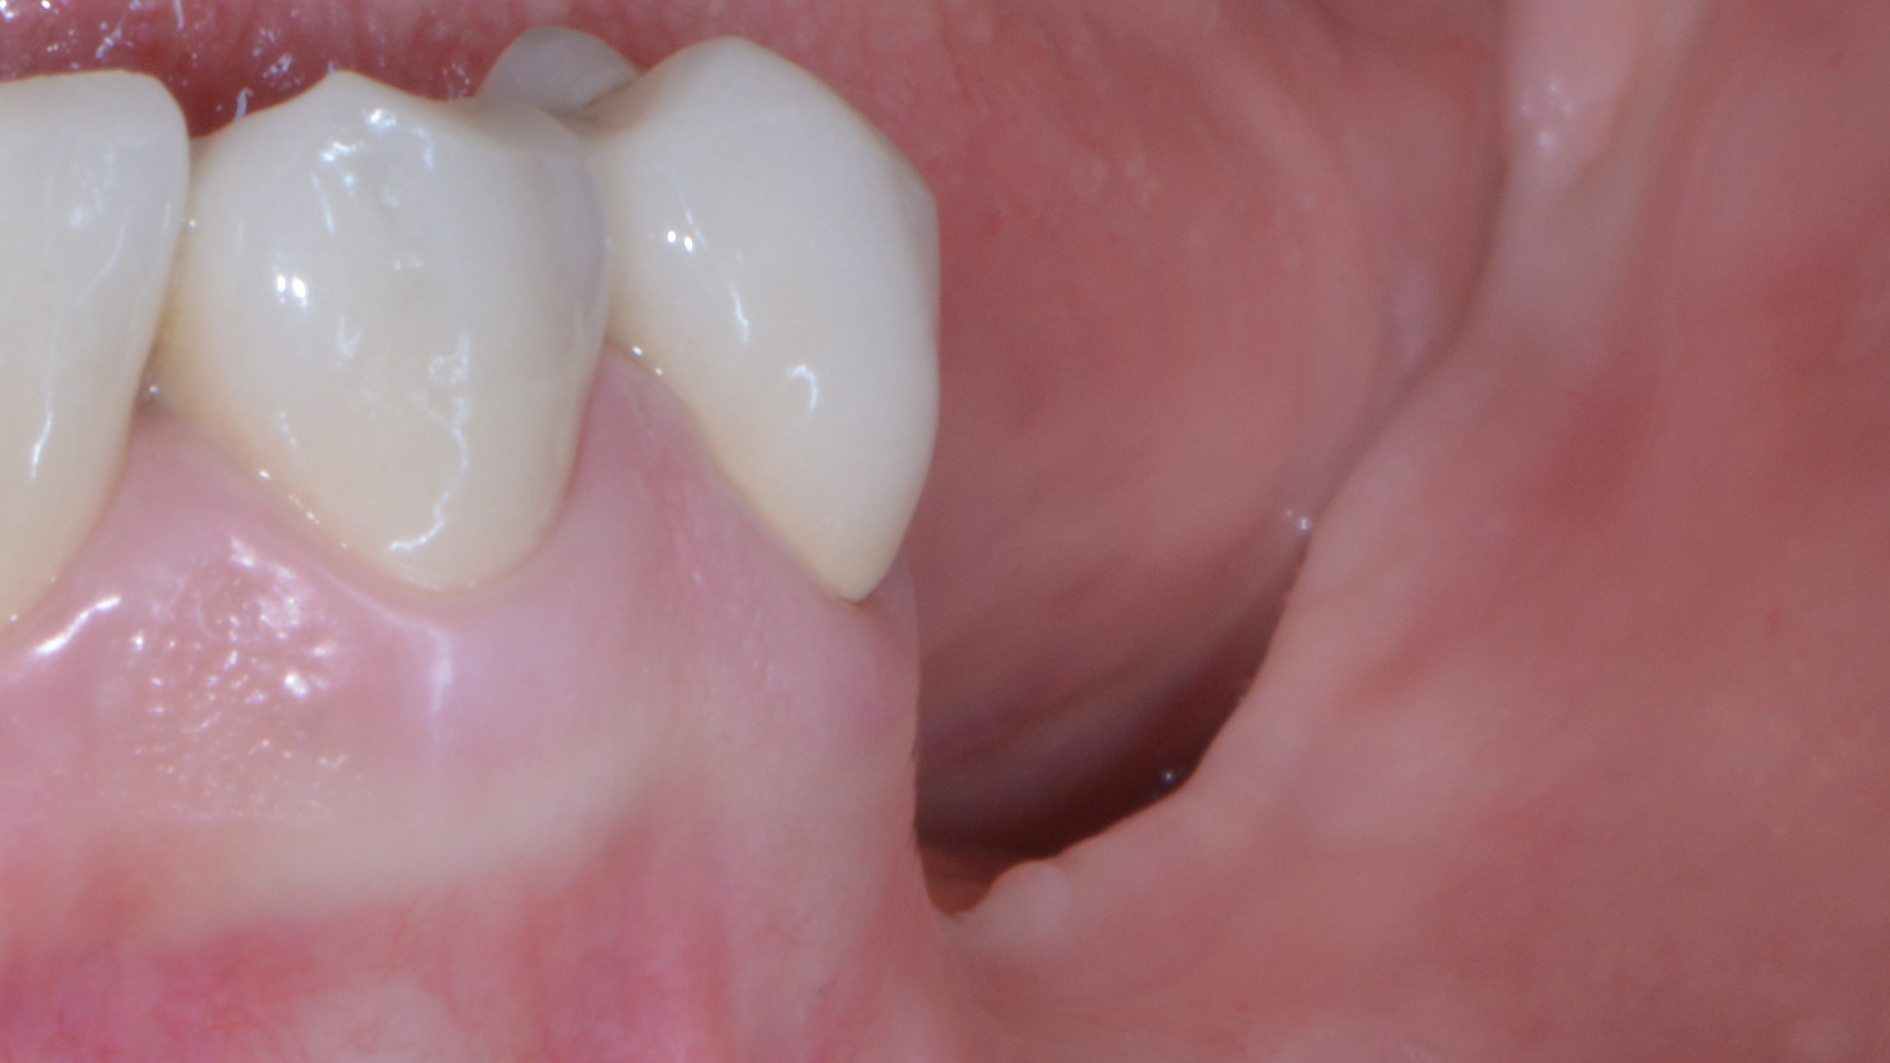

Come credi che si possa risolvere un caso come questo…

o come questo…

senza tecniche di chirurgia avanzata?